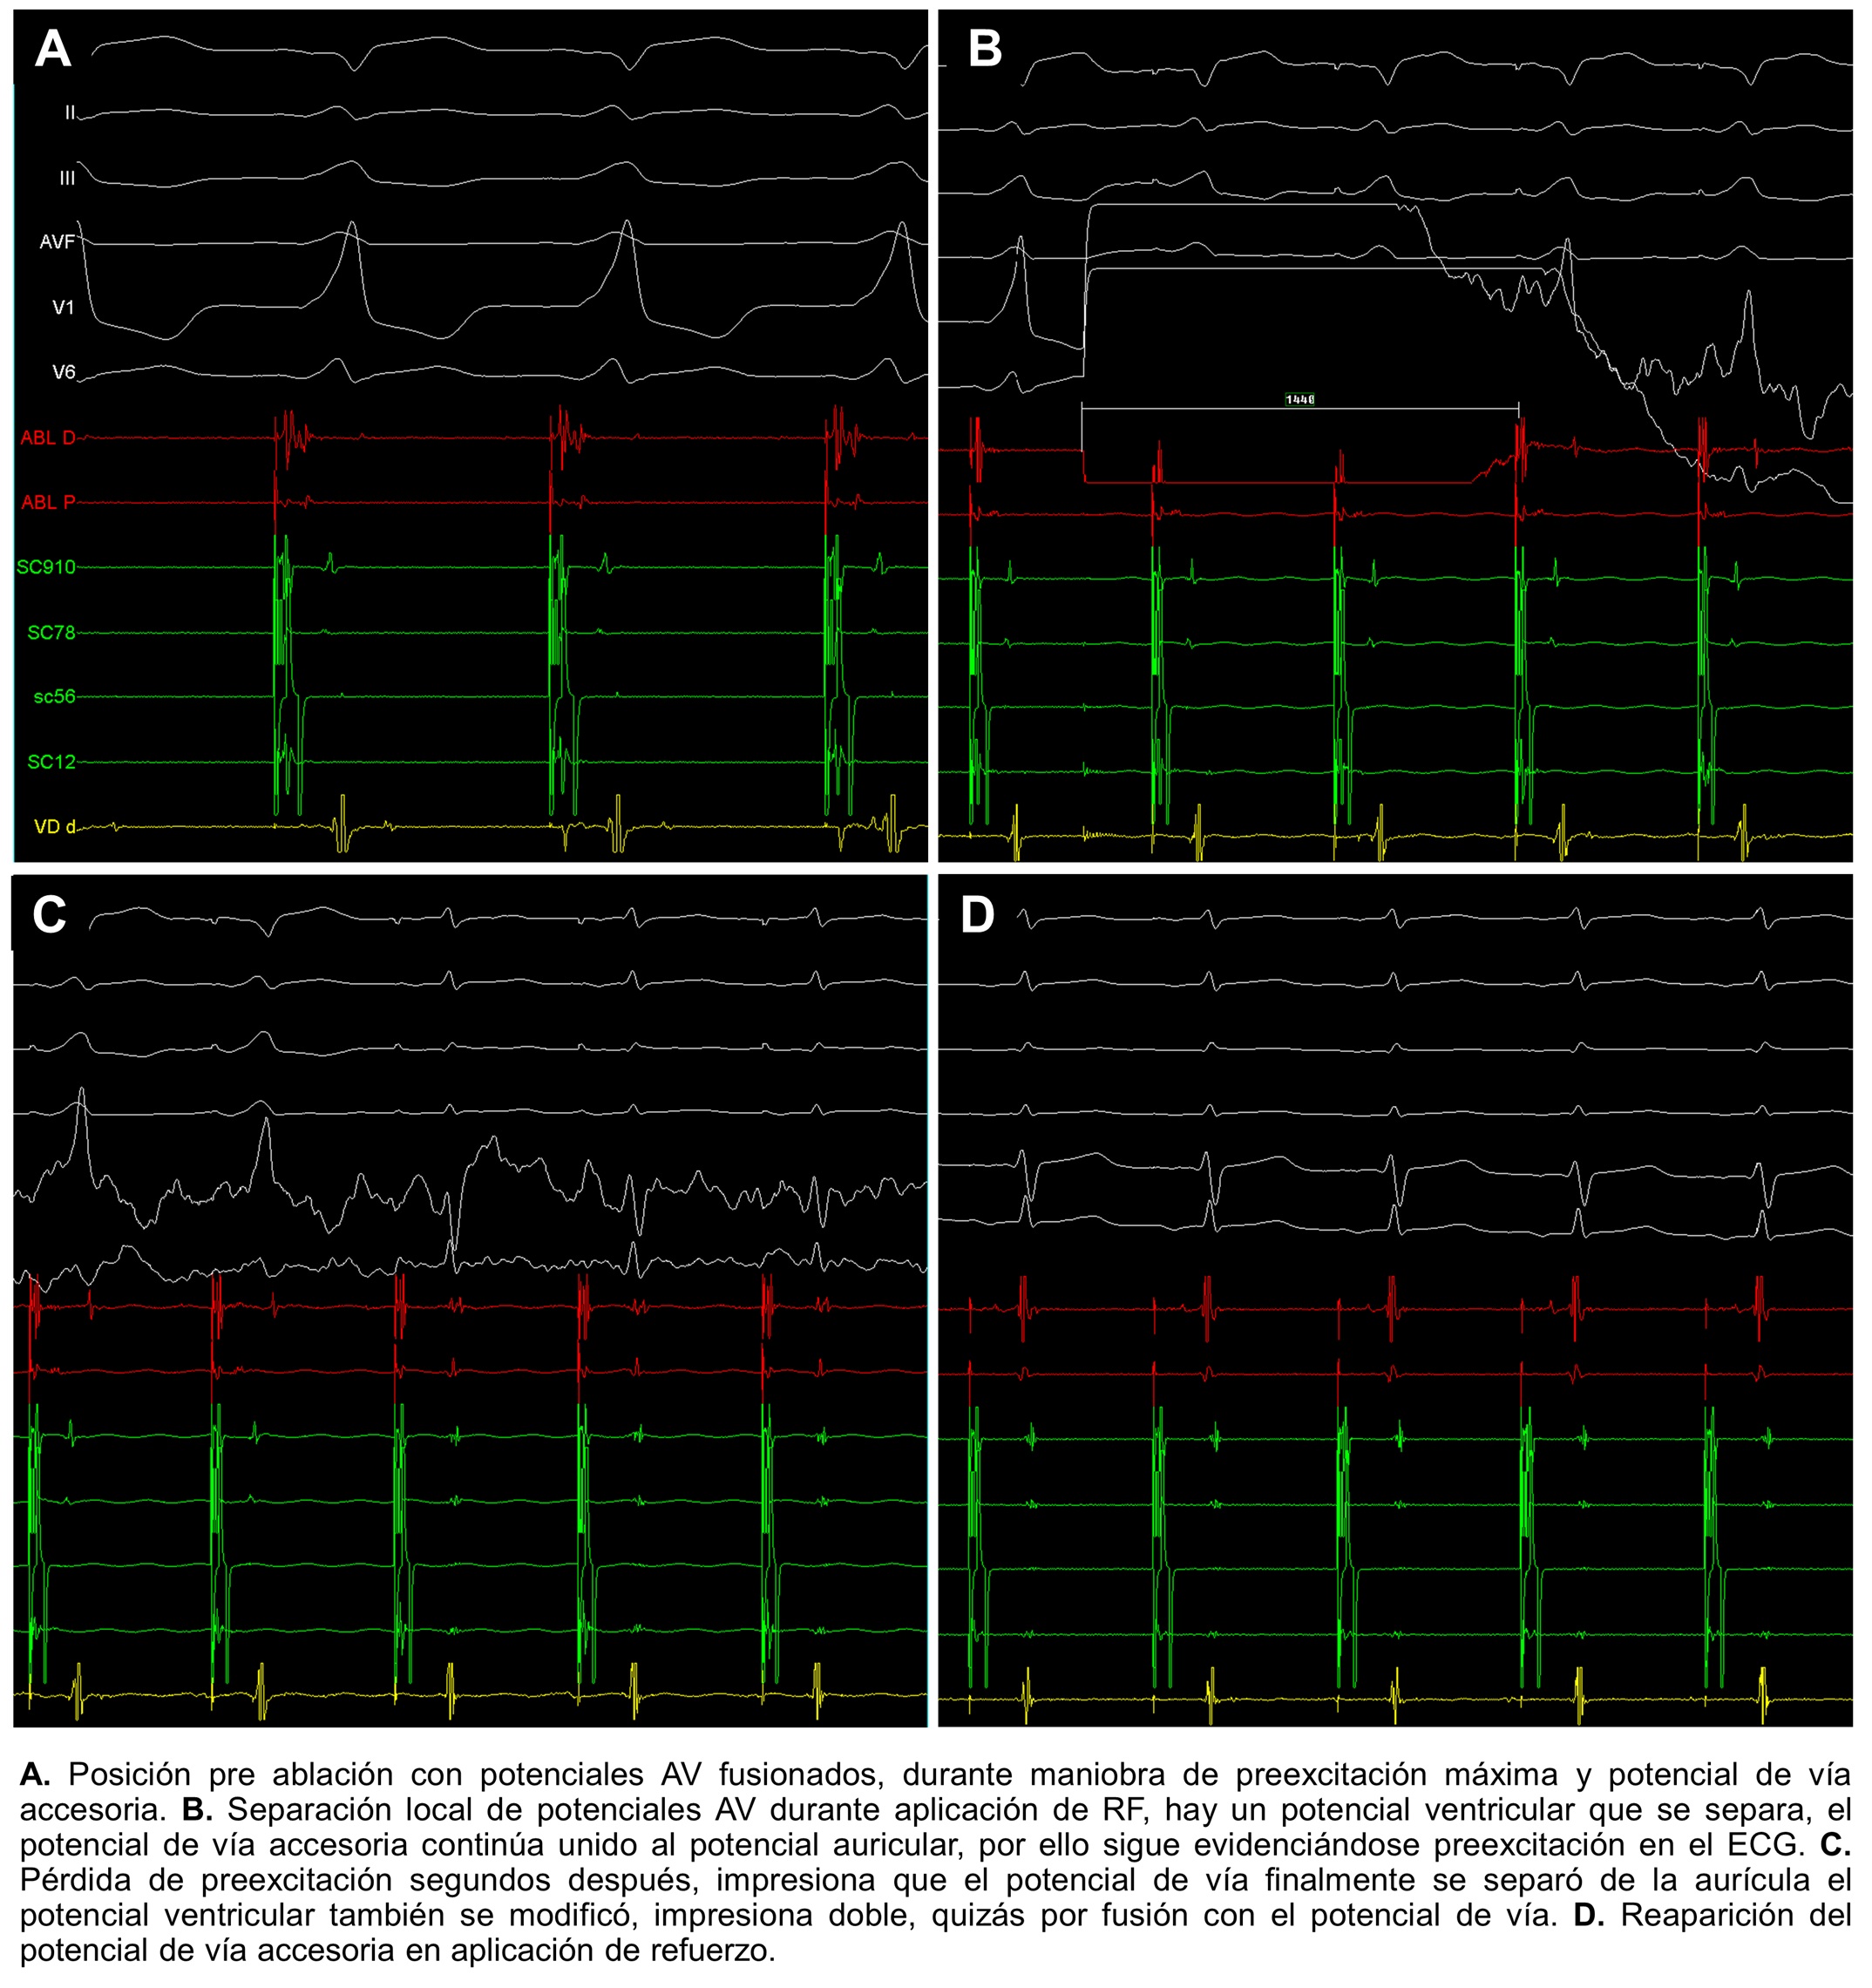

Introducción: El síndrome de preexcitación es la principal causa de taquicard...